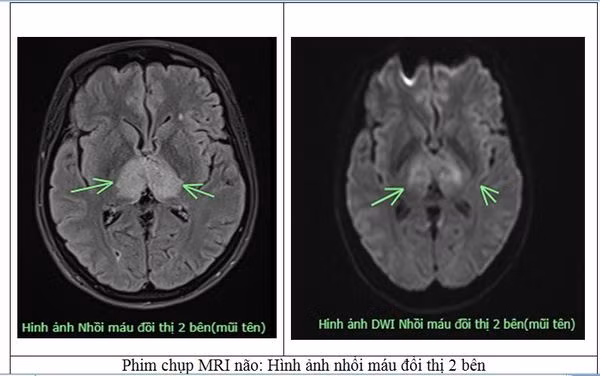

Người bệnh nữ, 38 tuổi, trú tại xã Sơn Hùng, huyện Thanh Sơn, Tỉnh Phú Thọ. Trước vào viện 4 ngày, người bệnh xuất hiện đau đầu, tự uống thuốc tại nhà nhưng không đỡ, sau đó ý thức chậm hơn, được gia đình đưa vào Bệnh viện Đa khoa tỉnh Phú Thọ trong tình trạng ý thức chậm chạp, Glasgow 13 điểm, tự thở, yếu tứ chi. Người bệnh được các bác sĩ chỉ định chụp MRI, kết quả có hình ảnh nhồi máu não tại vị trí đồi thị 2 bên.

Nhận thấy nhồi máu đồi thị 2 bên là tổn thương khá bất thường, các bác sĩ của Trung tâm Đột quỵ đã hội chẩn và đặt ra nghi vấn về 1 bệnh lý khá hiếm gặp, bệnh lý “Huyết khối tĩnh mạch não”.

Người bệnh được chỉ định chụp MRI sọ não có dựng xoang tĩnh mạch (TOP2D), xét nghiệm đông máu D-dimer. Kết quả xác định đây là 1 trường hợp “Huyết khối tĩnh mạch não”.

Kết luận: Hình ảnh huyết khối tĩnh mạch xoang ngang phải, xoang dọc trên, tĩnh mạch xoang thẳng lan theo tĩnh mạch não lớn và tĩnh mạch đồi thị hai bên, có phù não đồi thị hai bên và ổ thiếu máu não đồi thị phải.